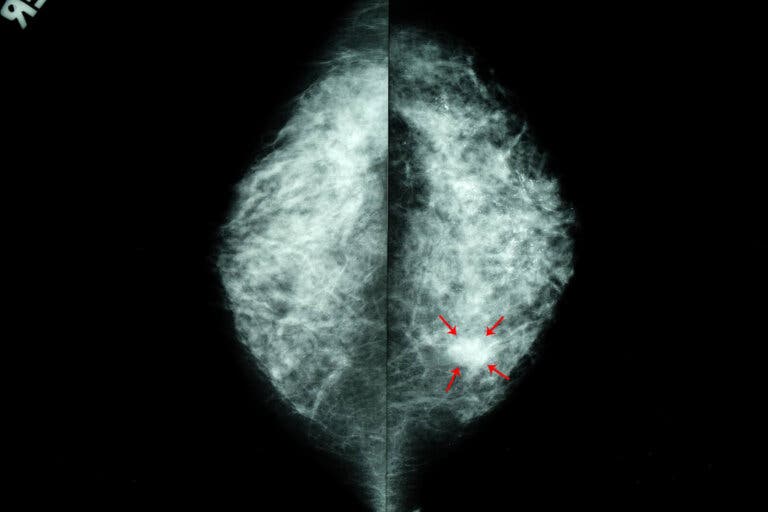

Como indica la literatura científica, las calcificaciones mamarias son pequeños depósitos de calcio que se ubican en una o ambas mamas. Constituyen uno de los hallazgos radiológicos más frecuentes. En la mamografía se ven como pequeñas manchas o puntos blancos. Es muy habitual que se encuentren en mujeres mayores de 50 años.

- Macrocalcificaciones. Se ven como grandes manchas o líneas blancas en la mamografía. Rara vez corresponden a un estado precanceroso o de cáncer. Generalmente solo se les hace un seguimiento mínimo.

- Microcalcificaciones. Aparecen como partículas blancas, muy finas, similares a un grano de sal. Por lo general no son cancerosas, pero si presentan algunos patrones específicos deben examinarse con mayor cuidado.

Lo usual es que si las calcificaciones mamarias son sospechosas se realice una segunda mamografía con vistas aumentadas, para descartar o ratificar las sospechas. En este último caso, lo más común es que se ordene una biopsia. En cualquier caso, la mamografía deberá repetirse periódicamente.